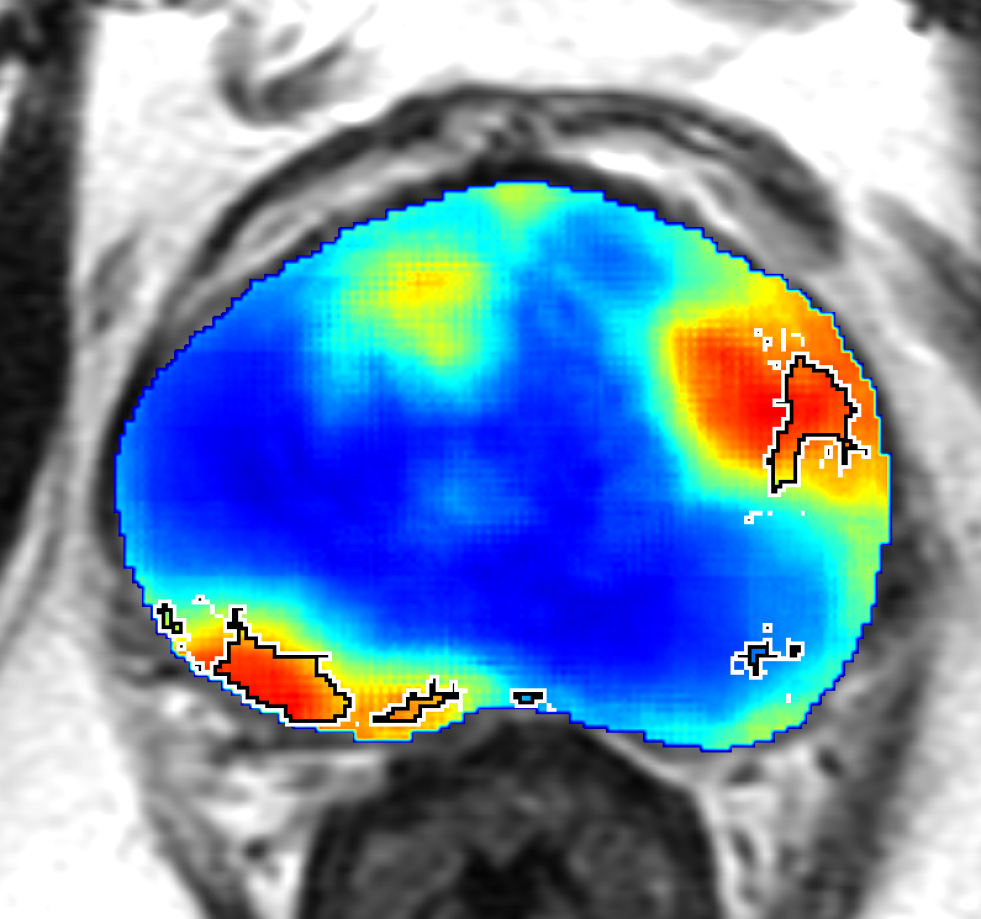

Training: From the 66 patients in the training cohort, we sampled all the cancer pixels from within the prostate, and randomly sampled an equal number of non-cancer pixels, also from within the prostate, thereby generating a training set of pixels, with equal number of cancer and non-cancer pixels. This ensured that we train the CorrNet with a balanced dataset of two classes. We used to weigh the cross-correlation error higher than the reconstruction errors. We chose a squared error loss for the reconstruction errors. We trained the CorrNet model with varying hidden layer dimensions, namely: . For each , we used a learning rate , and 300 training epochs. Figure 2 shows CorrNet representations of an example MRI slice, with .

Qualitative Evaluation: Figure 4 shows the same slice as in Figure 2 with aligned T2W, ADC, and histopathology images, and prediction results using current state-of-the-art method [4], our CorrSigNet() and CorrSigNet(T2W, ADC, ) models. It may be noted that [4] fails to detect the cancerous regions on the left and right of the images, while the CorrNet representations alone can identify the cancer regions, and when combined with T2W and ADC images, they predict the cancer regions with high probability. It may also be noted that CorrSigNet(T2W, ADC, ) shows fewer false positives than [4]. This example shows the strength of learning correlated MRI signatures in identifying subtle, and sometimes MRI-invisible cancers. Figure 5 shows more example slices from different patients, comparing the state-of-the-art approach [4] and our prediction results with CorrSigNet(T2W, ADC, ). We note that our model with correlated features (1) can identify subtle and smaller cancer regions, (2) have better overlap with ground truth cancer labels, and (3) have fewer false positives.